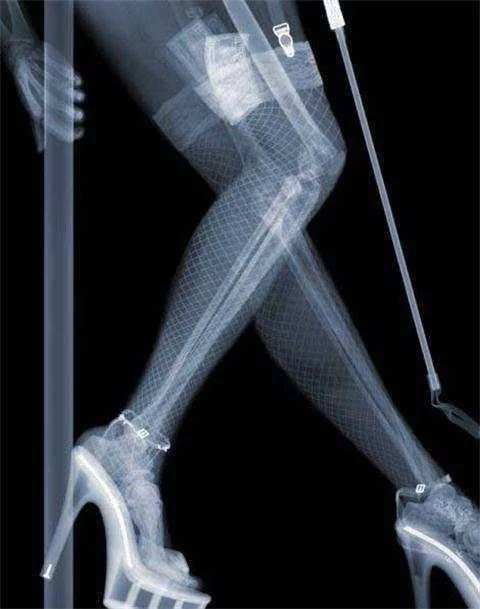

一些女性可能會認為,如(rú)果在通過安全檢查(chá)時被儀器(qì)看到,身為女性會很尷尬。經(jīng)過調查後才清(qīng)楚,安(ān)檢實際上(shàng)分為兩(liǎng)種,第(dì)一種是檢查乘客(kè)的行李,第二種是檢查乘客身上是否有危險品(pǐn)。每個安全檢查儀器就像醫院的x光片。掃描後,它將被投射到(dào)電腦上。雖然它隻是一個模糊(hú)的輪廓(kuò),但隻要它是危(wēi)險的,就可以立(lì)即被檢(jiǎn)測出來,然後顏色就會被識別出來。其餘的普通物品是(shì)灰色的。因此,女性同胞根本不用擔心這個問題。他們(men)根本看(kàn)不到個人(rén)隱私。在安檢過程中,安檢人員看起來就(jiù)像在醫院(yuàn)拍(pāi)攝一樣。男人和女人(rén)都是一樣的。他們看到(dào)的隻(zhī)是骨頭,不涉及隱私。